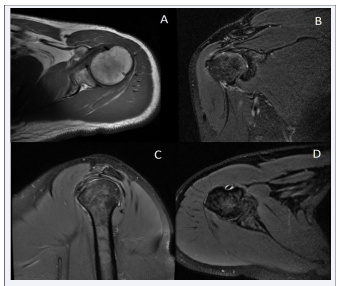

The auxiliary examination showed that the ultrasound of the bilateral shoulder joints revealed that there was partial bursa surface injury at the attachment site of the Greater Tuberosity of the Humerus muscle tendon on the right side and left side, thickening of the subacromial-subdeltoid bursa, and suspected bursitis. There was a lesion on the posterosuperior lip. The magnetic resonance image of the right shoulder joint revealed the following pathological changes: 1) a pseudo-cyst formation at the attachment site of the Greater Tuberosity of the Humerus muscle tendon; 2) degeneration of the supraspinatus muscle tendon; and 3) a small amount of effusion around the subacromial-subdeltoid bursa, the infraspinatus muscle tendon, and the long head tendon of the biceps brachii [Figure 1].

Figure 1 MRI images of the shoulder joint in patient 1 (A) –pseudocyst formation at the attachment of the greater tuberosity tendon of the  humerus. (B) –degeneration of the supraspinatus tendon and subscapularis muscle edema. (C-D) –a small amount of fluid accumulation around the  subacromial-subdeltoid bursa and the long head of the biceps tendon)

Figure 1: MRI images of the shoulder joint in patient 1 (A) –pseudocyst formation at the attachment of the greater tuberosity tendon of the humerus. (B) –degeneration of the supraspinatus tendon and subscapularis muscle edema. (C-D) –a small amount of fluid accumulation around the subacromial-subdeltoid bursa and the long head of the biceps tendon)